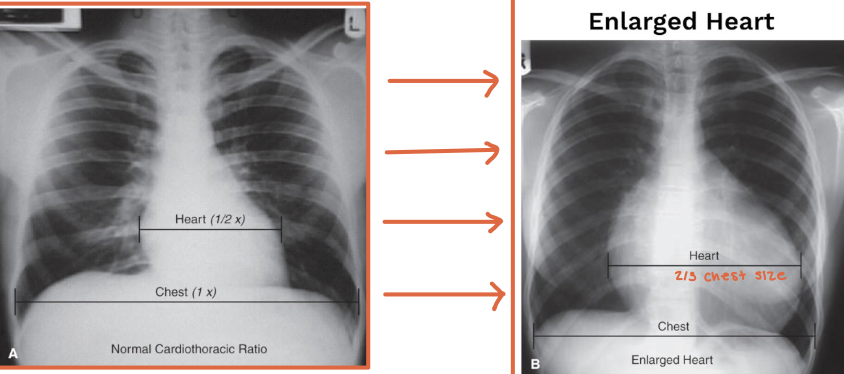

What is the cardiothoracic ratio?

A radiographic estimate of heart size

What is a normal adult cardiothoracic ratio?

The heart width should be less than half the chest width at the level of the diaphragm